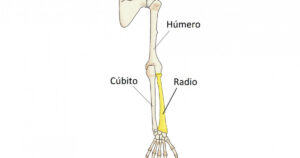

Las fracturas pediátricas de mayor frecuencia son las de clavícula y de húmero distal (parte más cercana al codo) en los menores de 5 años. Por otro lado, las de huesos de la mano y radio distal (parte más cerca a la mano) son más comunes en niños de 5-17 años. Estas fracturas pueden darse como consecuencia de un accidente deportivo o una caída de altura.

Otra de las fracturas comunes en esta población son:

Antebrazo (cúbito, radio o ambas)

Éstas también podrían resultar como consecuencia de un accidente deportivo o una caída de altura. Se podrá observar una deformidad evidente y dolor. Dependerá de la lesión el tratamiento a recomendar, que podría ir desde inmovilizar el área hasta colocar un yeso.

Húmero

Las fracturas de húmero distal pueden deberse a un traumatismo directo asociado a lesión de partes blandas o un traumatismo indirecto por una caída sobre la mano. Con estas fracturas se podrá observar una pérdida de movilidad articular (debida al grado de la lesión), dolor y deformación.